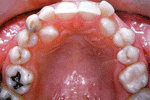

มาถึง การจัดฟันด้านใน

การจัดฟันแบบใสและขั้นตอนการจัดฟันมีรูปคนน่ารักจัดฟันด้วย    การจัดฟันแบบใสและขั้นตอนการจัดฟันมีรูปคนน่ารักจัดฟันด้วย       การจัดฟันแบบใสและขั้นตอนการจัดฟันมีรูปคนน่ารักจัดฟันด้วย